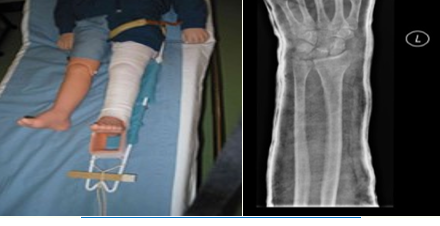

Plaster of Paris cast

Name this fixation technique

K-wire fixation